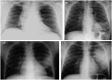

The association of tuberculosis (TB) with human immunodeficiency virus (HIV) infection and acquired immune deficiency syndrome over the past several years has become an emerging syndemic. Approximately 10% of people living with HIV (PLHIV) with latent TB infection will develop active TB disease each year. In this review, we highlight that this phenomenon is not limited to high endemic regions, such as Afro-Asian nations, but globalization/migration is causing increased case detection even in developed nations, such as the United States. Active screening should be performed for TB in PLHIV. A high degree of clinical suspicion for TB is warranted in PLHIV presenting with fever, cough, and unintentional weight loss. HIV-Mycobacterium tuberculosis (MTB) coinfection is often paucibacillary, precluding diagnosis by conventional diagnostics and/or smear microscopy/culture. Improved detection of pulmonary and extrapulmonary TB is now possible by incorporation of the GeneXPERT MTB/RIF assay (Cepheid Inc., Sunnyvale, CA, USA). The World Health Organization recommends instituting immediate therapy for MTB, in conjunction with ongoing or newly introduced anti-retroviral therapy. Vigilance is required to detect drug-induced organ injuries, and early-treatment-induced immune reconstitution inflammatory syndrome. Collaborating MTB and HIV activities in concentrated HIV epidemic settings should become a high public health priority.